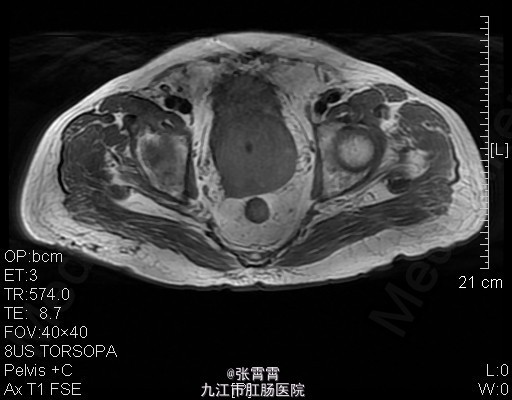

6、诊断:前列腺增生,膀胱结石,高血压 7、处理:住院后完善相关检查,盆腔MR平扫+增强扫描:1、前列腺增生并癌变,考虑侵犯前列腺包膜。2、慢性膀胱炎。3、双侧腹股沟区多发稍大淋巴结,考虑前列腺癌(早期)。诊断为前列腺增生。目前已排除手术禁忌证。予术前检查后行经尿道前列腺剜切术+耻骨上膀胱造瘘术+切开取石术,手术顺利,术后组织病理检查示前列腺增生,术后恢复顺利。